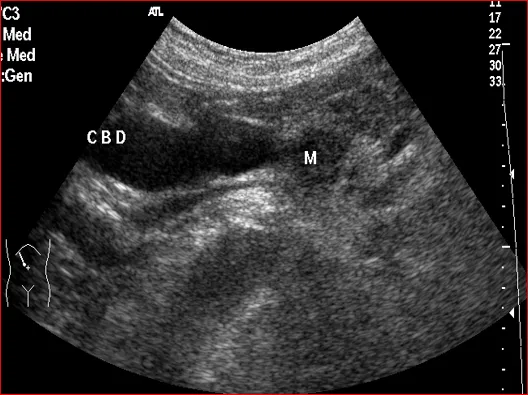

上腹部斜纵切显示胰头癌压迫胆总管

壶腹部低回声占位,胆总管扩张